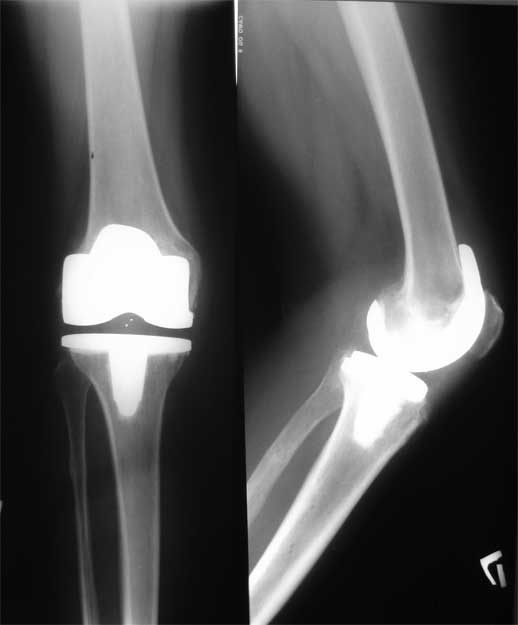

Вложение не в текстовом формате было извлечено…

Имя     : 2.jpg

Тип     : image/jpeg

Размер  : 6392 байтов

Описание: отсутствует

Url     : http://weborto.net:8080/pipermail/ortho/attachments/20090513/64886c60/attachment-0004.jpg